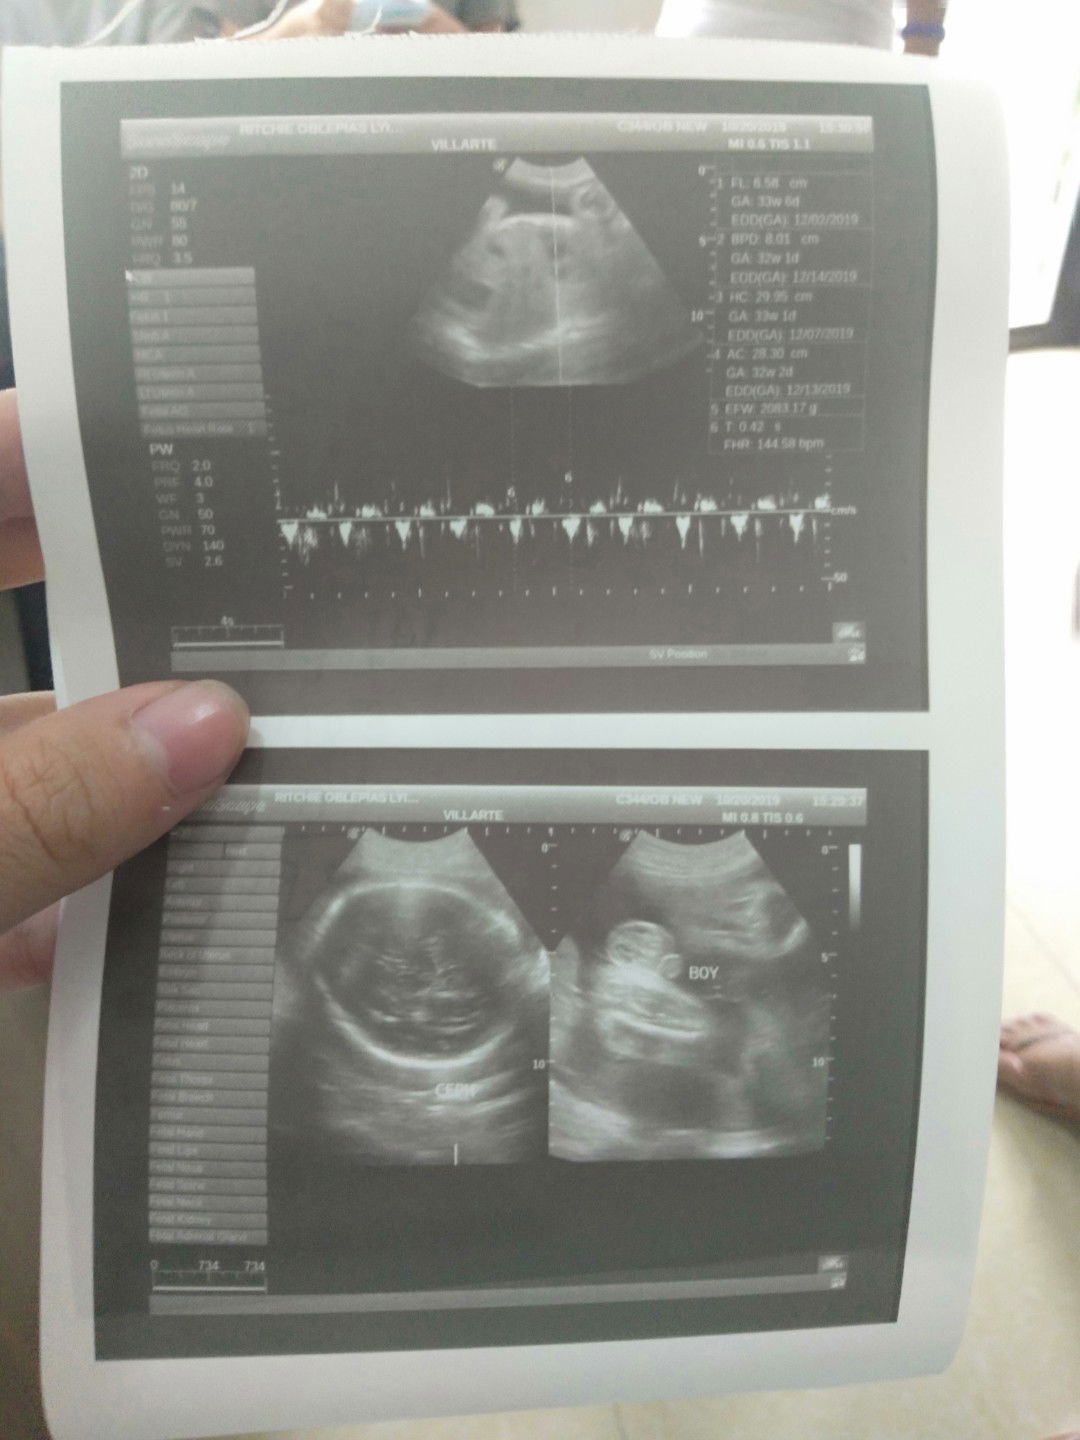

Subra saya yung hirap ko kagabe sa pag lalabor lumabas sya 11 nang gabe nahirapan ako kasi malaki si baby 3.7kls . . Grabe worth it talaga pag nakita muna si baby mawawala pagod at sakit 2nd baby kuna po ito panganay ko babae 3year old baby andrew namin nairaos kuna din thank you sa mga mommys dito na nag advice sakin???????